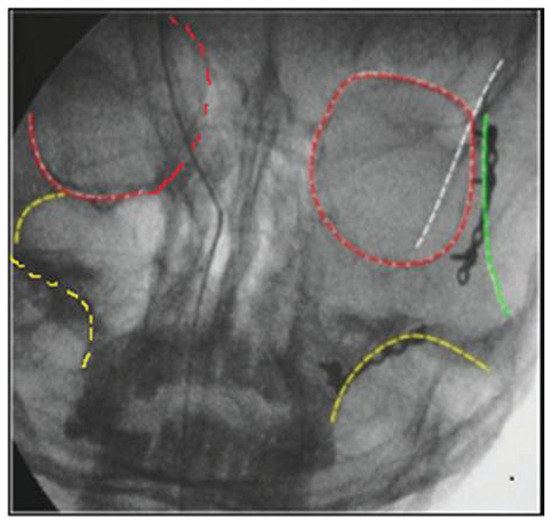

Figure 11.

C-arm image after reduction and before fixation.

Figure 12.

C-arm image after fixation with markings.

Based on preoperative orbital volume of both eyes assessed through three-dimensional CT, greater than 18 to 20% of orbital volume difference of injured orbit [6] compared with normal eye and patients evident with orbital floor fracture with a defect were planned for exploration of orbital floor. A study was planned in which unilateral displaced zygomatic complex fractures were treated with intraoperative assessment of the reduction with C-arm. All patients were operated by same surgeon and the intraoperative procedure is as follows: Preoperative images (Figure 6) were done with standardized settings (73 kV, 0.32 mA) of the C-arm to obtain images at 0 and 30 degrees (Figure 7 and Figure 8). The sutural contacts of zygoma were assessed and fracture segments were identified at 0-degree view and malar projection and zygomatic arch alignment at 30-degree view. An incision at frontozygomatic area and intraoral vestibular incision were given and fracture was reduced and the reduction was confirmed with C-arm (Figure 9 and Figure 10) at five mentioned areas and ZMC fracture [7] was fixed at two or three points (Figure 13). The continuity of the Dolan lines [8] was used to confirm the reduction in the water view image displayed on the monitor (Figure 11 and Figure 12). The continuity of the innominate line helped in aligning the sphenozygomatic suture. If the surgeon feels that infraorbital rim continuity is not achieved on C-arm image, then infraorbital rim is exposed and fixation is done. By this way, unnecessary exploration of the infraorbital rim can be avoided and in cases where orbital floor exploration based on preoperative CT evaluation, exploration is done only after primary fixation and assessment by C-arm. Minimal exposure principle is followed. In the group of patients operated without intraoperative imaging, zygoma was assessed at three points and was reduced in the frontozygomatic suture region, zygomaticomaxillary buttress, and the infraorbital rim.

We assessed the reduction in C-arm images with the help of Dolan lines which was first popularized by Dolan et al. [16] We found that intraoperative C-arm is very useful to view innominate line and assess the proper reduction of ZMC fractures at the sphenozygomatic suture. As Gruss et al. [17] proposed that zygomatic arch is the key in mid-facial fracture repair, in our study, zygomatic arch with malar prominence is assessed in every case at preoperative, intraoperative, and postreduction periods.